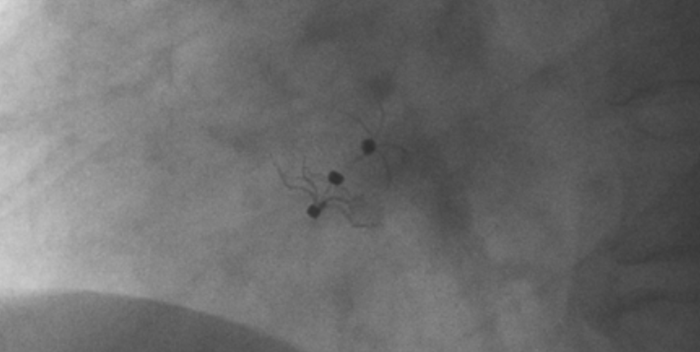

術(shù)中造影顯示患者為PFO且長隧道型,目前市場上已商業(yè)化的PFO封堵器難以滿足該患者解剖結(jié)構(gòu)封堵需求。迪創(chuàng)醫(yī)療自主研發(fā)的OmniSeal PFO封堵器自適應性雙盤貼合設(shè)計能廣泛適應不同PFO隧道長度的解剖結(jié)構(gòu)和形態(tài),其雙盤外包覆式阻流和隧道內(nèi)填充阻流相結(jié)合的雙重阻流設(shè)計,可為此患者實現(xiàn)有效封堵。與此同時,OmniSeal首創(chuàng)的完全可穿刺式設(shè)計,也為此患者最大程度地保留了房間隔區(qū)域穿刺通道,以實現(xiàn)全兼容未來可能的左心系統(tǒng)二次介入術(shù)。術(shù)終造影和心臟超聲顯示封堵完全、效果良好。作為OmniSeal的首例臨床應用,本次手術(shù)的順利完成和優(yōu)異效果充分體現(xiàn)了產(chǎn)品的設(shè)計創(chuàng)新優(yōu)勢。

影像顯示試驗器械適應性貼合于房間隔兩側(cè)且穩(wěn)定